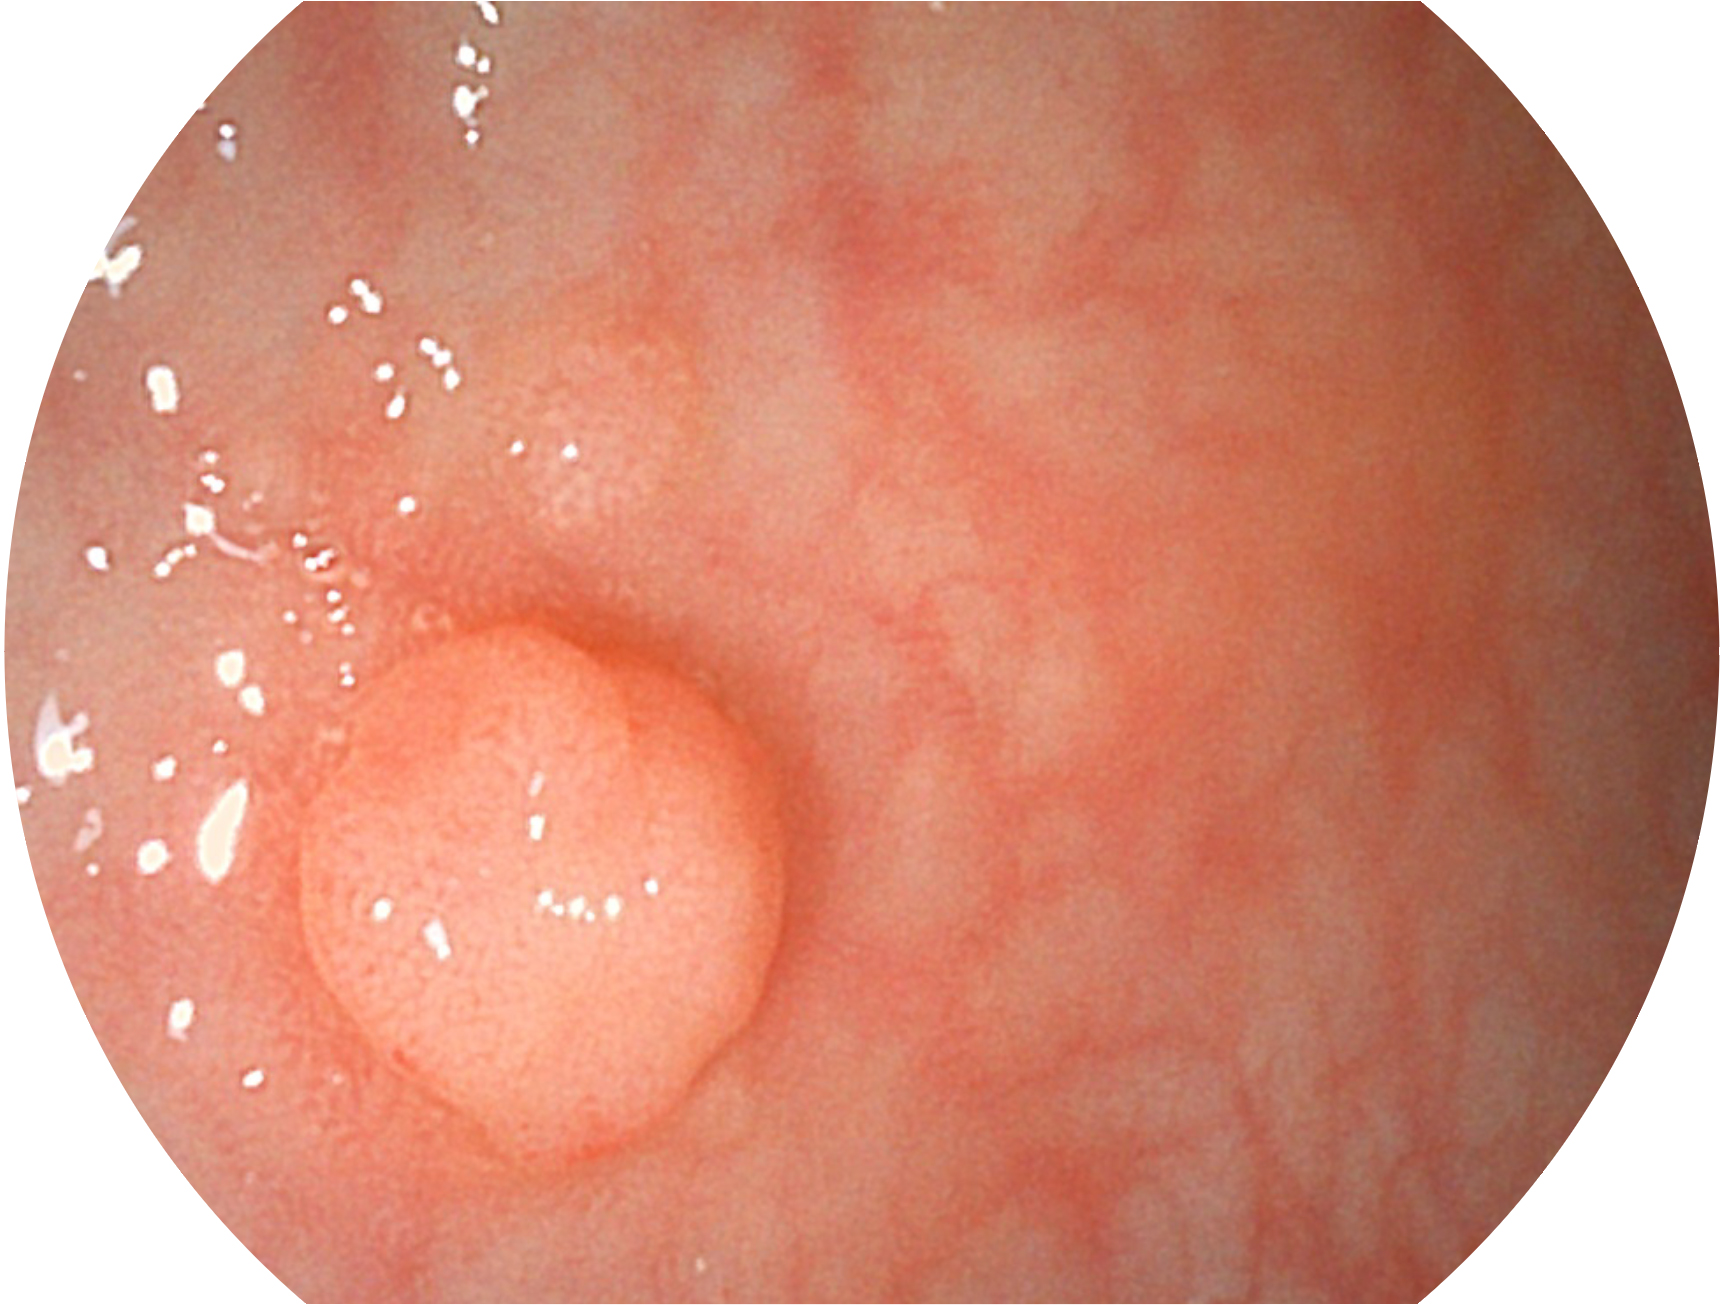

• 白光圖像 SFI圖像